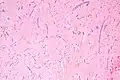

Atrial myxoma and myocardium. H&E stain.

Atrial myxoma and myocardium. H&E stain. -